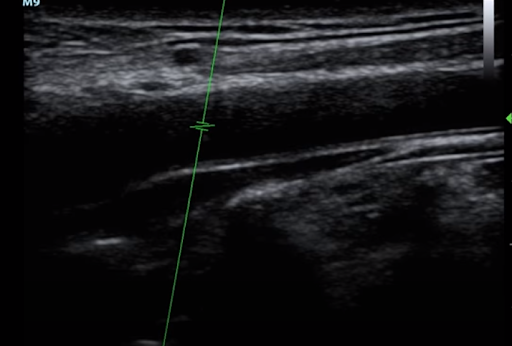

(b) Next rotate the probe into the longitudinal axis to get the view needed for the measurements

Slide up the vessel until you see the carotid bulb (that is the slightly wider portion seen on the left side of the carotid in the above image) Usually found 2-3 cm was below the bifurcation of the CCA into the external and internal carotid arteries